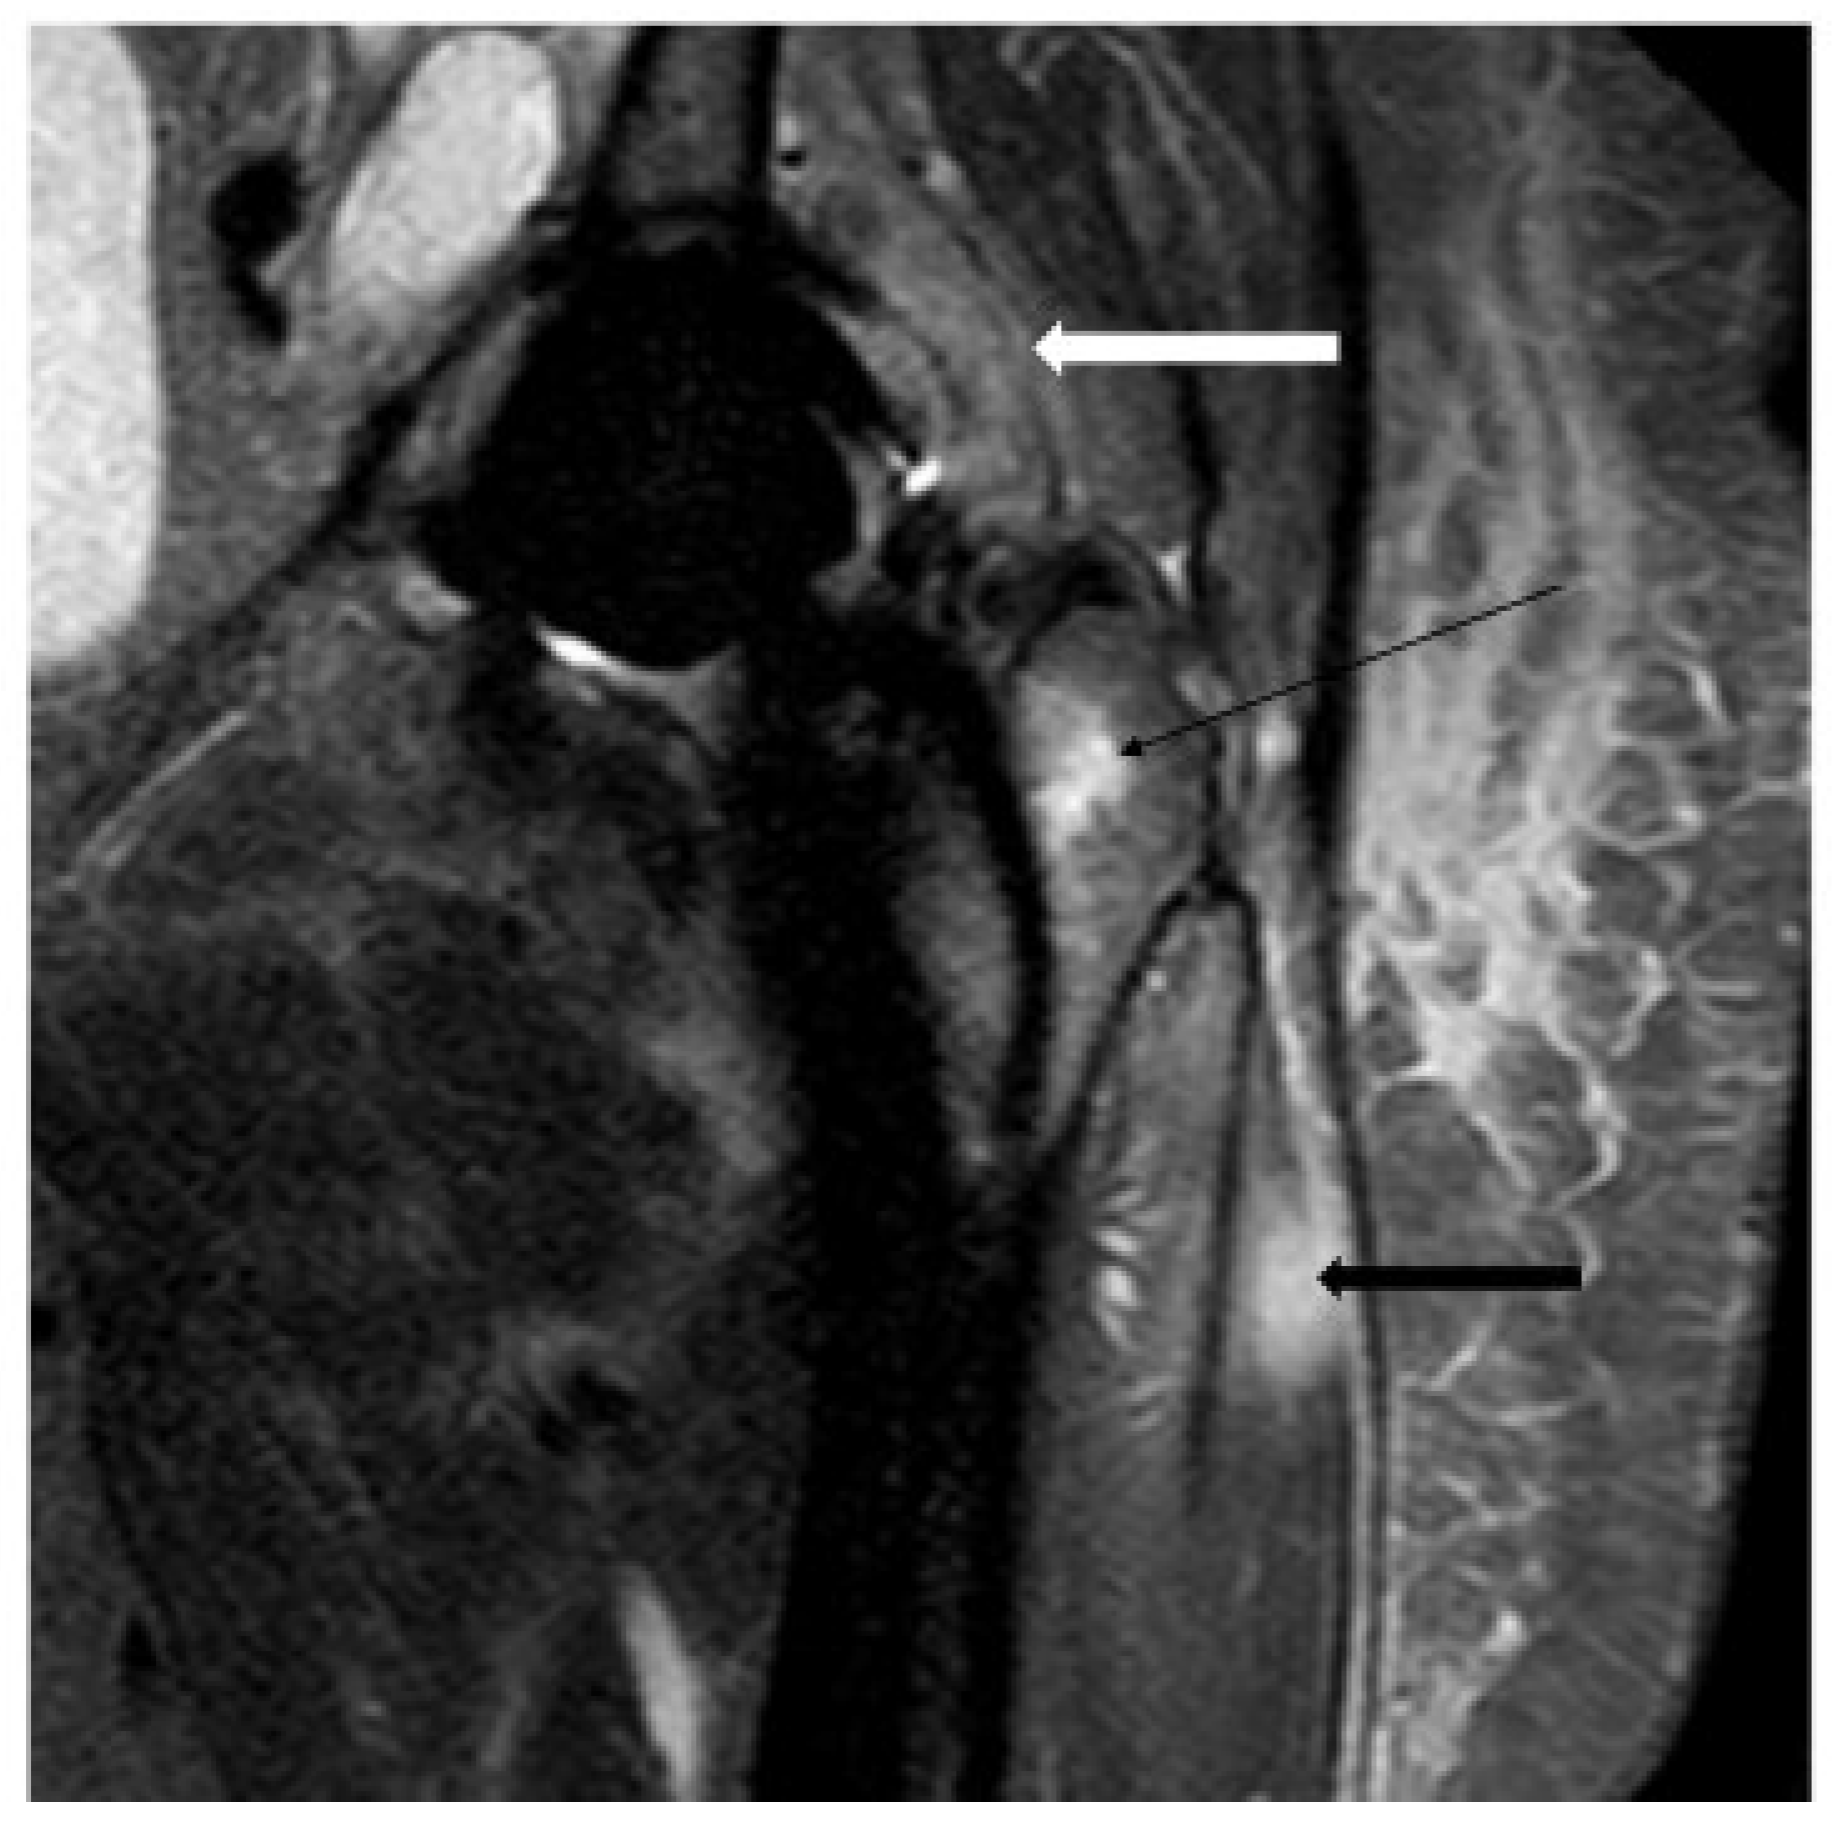

4.4. Magnetic Resonance Imaging

- Galley, J.; Sutter, R.; Stern, C.; Filli, L.; Rahm, S.; Pfirrmann, C.W. Diagnosis of periprosthetic hip joint infection using MRI with metal artifact reduction at 1.5 T. Radiology 2020, 296, 98–108. [Google Scholar] [CrossRef] [PubMed]

- Schwaiger, B.J.; Gassert, F.T.; Suren, C.; Gersing, A.S.; Haller, B.; Pfeiffer, D.; Dangelmaier-Dawirs, J.; Roski, F.; von Eisenhart-Rothe, R.; Prodinger, P.M. Diagnostic accuracy of MRI with metal artifact reduction for the detection of periprosthetic joint infection and aseptic loosening of total hip arthroplasty. Eur. J. Radiol. 2020, 131, 109253. [Google Scholar] [CrossRef]

- Inaoka, T.; Kitamura, N.; Sugeta, M.; Nakatsuka, T.; Ishikawa, R.; Kasuya, S.; Sugiura, Y.; Nakajima, A.; Nakagawa, K.; Terada, H. Diagnostic value of advanced metal artifact reduction magnetic resonance imaging for periprosthetic joint infection. J. Comput. Assist. Tomogr. 2022, 46, 455–463. [Google Scholar] [CrossRef]

- Belmatoug, N.; Crémieux, A.-C.; Bleton, R.; Volk, A.; Saleh-Mghir, A.; Grossin, M.; Garry, L.; Carbon, C. A new model of experimental prosthetic joint infection due to methicillin-resistant Staphylococcus aureus: A microbiologic, histopathologic, and magnetic resonance imaging characterization. J. Infect. Dis. 1996, 174, 414–417. [Google Scholar] [CrossRef]

- Jiang, M.-h.; He, C.; Feng, J.-m.; Li, Z.-h.; Chen, Z.; Yan, F.-h.; Lu, Y. Magnetic resonance imaging parameter optimizations for diagnosis of periprosthetic infection and tumor recurrence in artificial joint replacement patients. Sci. Rep. 2016, 6, 36995. [Google Scholar] [CrossRef] [PubMed]

- Plodkowski, A.J.; Hayter, C.L.; Miller, T.T.; Nguyen, J.T.; Potter, H.G. Lamellated hyperintense synovitis: Potential MR imaging sign of an infected knee arthroplasty. Radiology 2013, 266, 256–260. [Google Scholar] [CrossRef]

- Gao, Z.; Jin, Y.; Chen, X.; Dai, Z.; Qiang, S.; Guan, S.; Li, Q.; Huang, J.; Zheng, J. Diagnostic value of MRI lamellated hyperintense synovitis in periprosthetic infection of hip. Orthop. Surg. 2020, 12, 1941–1946. [Google Scholar] [CrossRef] [PubMed]

- He, C.; Lu, Y.; Jiang, M.; Feng, J.; Wang, Y.; Liu, Z. Clinical value of optimized magnetic resonance imaging for evaluation of patients with painful hip arthroplasty. Chin. Med. J. 2014, 127, 3876–3880. [Google Scholar] [CrossRef]

- Busch, A.; Jäger, M.; Beck, S.; Wegner, A.; Portegys, E.; Wassenaar, D.; Theysohn, J.; Haubold, J. Metal Artefact Reduction Sequences (MARS) in Magnetic Resonance Imaging (MRI) after Total Hip Arthroplasty (THA). BMC Musculoskelet. Disord. 2022, 23, 620. [Google Scholar] [CrossRef] [PubMed]